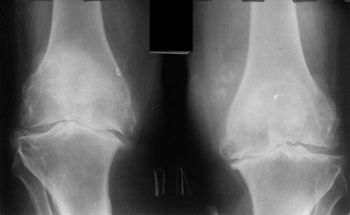

În urmă cu doi ani, am început să am dureri ușoare la genunchi și la șold. Durerea nu era gravă, nu i-am dat prea multă atenție... După cum se pare, bolile articulare sunt foarte grave și trebuie de luptat cu ele imediat, și a nu amăna cum am făcut-o eu! Într-o zi am simțit o durere ascuțită, dar nu foarte puternică, în genunchi, iar șoldul începea să mă doară într-adevăr tare . Am cumpărat câteva remedii și unguente și am început să le folosesc. Am răbdat durerea timp de aproximativ 1 săptămână, starea mea a început să se înrăutățească, durerea a devenit insuportabilă, a început o durere puternică în articulația șoldului, am luat decizia sa apelez la un specialist pentru prima dată. Nu a fost ieftină consultarea, iar specialistul meu s-a uitat la rezultate și a spus:

"De ce ai ignorat simptomele înainte? Aveți artroză! Dacă vreți să evitați să ajungeți într-un scaun cu rotile, trebuie să vă operați la șold și la genunchi!"

Efectele artrozei asupra cartilajului articulației genunchiului.

Din păcate, specialistul avea dreptate... După 2 luni era insuportabil de dureros să stau în picioare, remediile și analgezicele nu mai funcționau, deși cheltuisem o mulțime de bani pe ele, iar remediile îmi afectau grav stomacul și ficatul - am fost nevoită să renunț la ele! A trebuit să-mi cumpăr un scaun cu rotile și să-l folosesc pentru a mă deplasa prin casă... Specialistul meu a spus că artroza distruge cartilajul în 3 ani, dar părea să înceapă mult mai repede, cel mai interesant lucru este că nu simțeam durerea articulară, iar apoi, dintr-o dată, s-au agravat și, brusc, am ajuns într-un scaun cu rotile, fără nicio speranță de vindecare, îmi amintesc doar lacrimile care îmi veneau în ochi, a fost cea mai grea perioadă din viața mea......